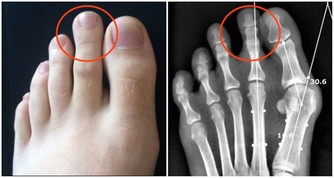

4.性早熟是個禍害

性早熟會導致孩子骨齡超前,雖然短時間內他們會比其他孩子高,

但是發育結束後,他們的最終身高會達不到平均標準。

所以當孩子有性早熟情況的時候,一定要找醫生。

平常家長不要讓孩子過早接觸不健康的信息,拒絕不健康的食品,減少激素的攝入。